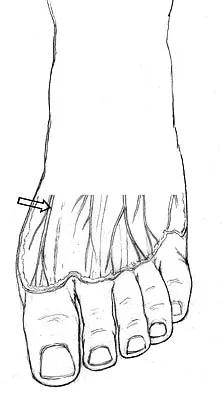

The pathophysiology of a claw toe deformity includes muscular imbalance caused by which of the following relatively strong structures?

Correct Answer: Extensor digitorum longus overpowering relatively weak intrinsics

The dynamic forces acting to maintain the position of the proximal phalanx at the head of the metatarsal are a balance between the extensor digitorum longus and the weaker intrinsic muscles. With hyperextension at the metatarsophalangeal joint, the intrinsic muscles become less efficient as plantar flexors. Consequently, the hyperextension deformity progresses in the metatarsophalangeal joint as the opposition of the intrinsic muscles to the extensor tendon lessens. This is in contrast to the situation in the interphalangeal joints, where the stronger flexors overpower the weaker intrinsic muscles, which act as the extensors. This combination of events leads to hyperextension at the metatarsophalangeal joint and flexion deformities at the interphalangeal joints, resulting in claw toe. Mizel MS, Yodlowski ML: Disorders of the lesser metatarsophalangeal Joints. J Am Acad Orthop Surg 1995;3:166-173.